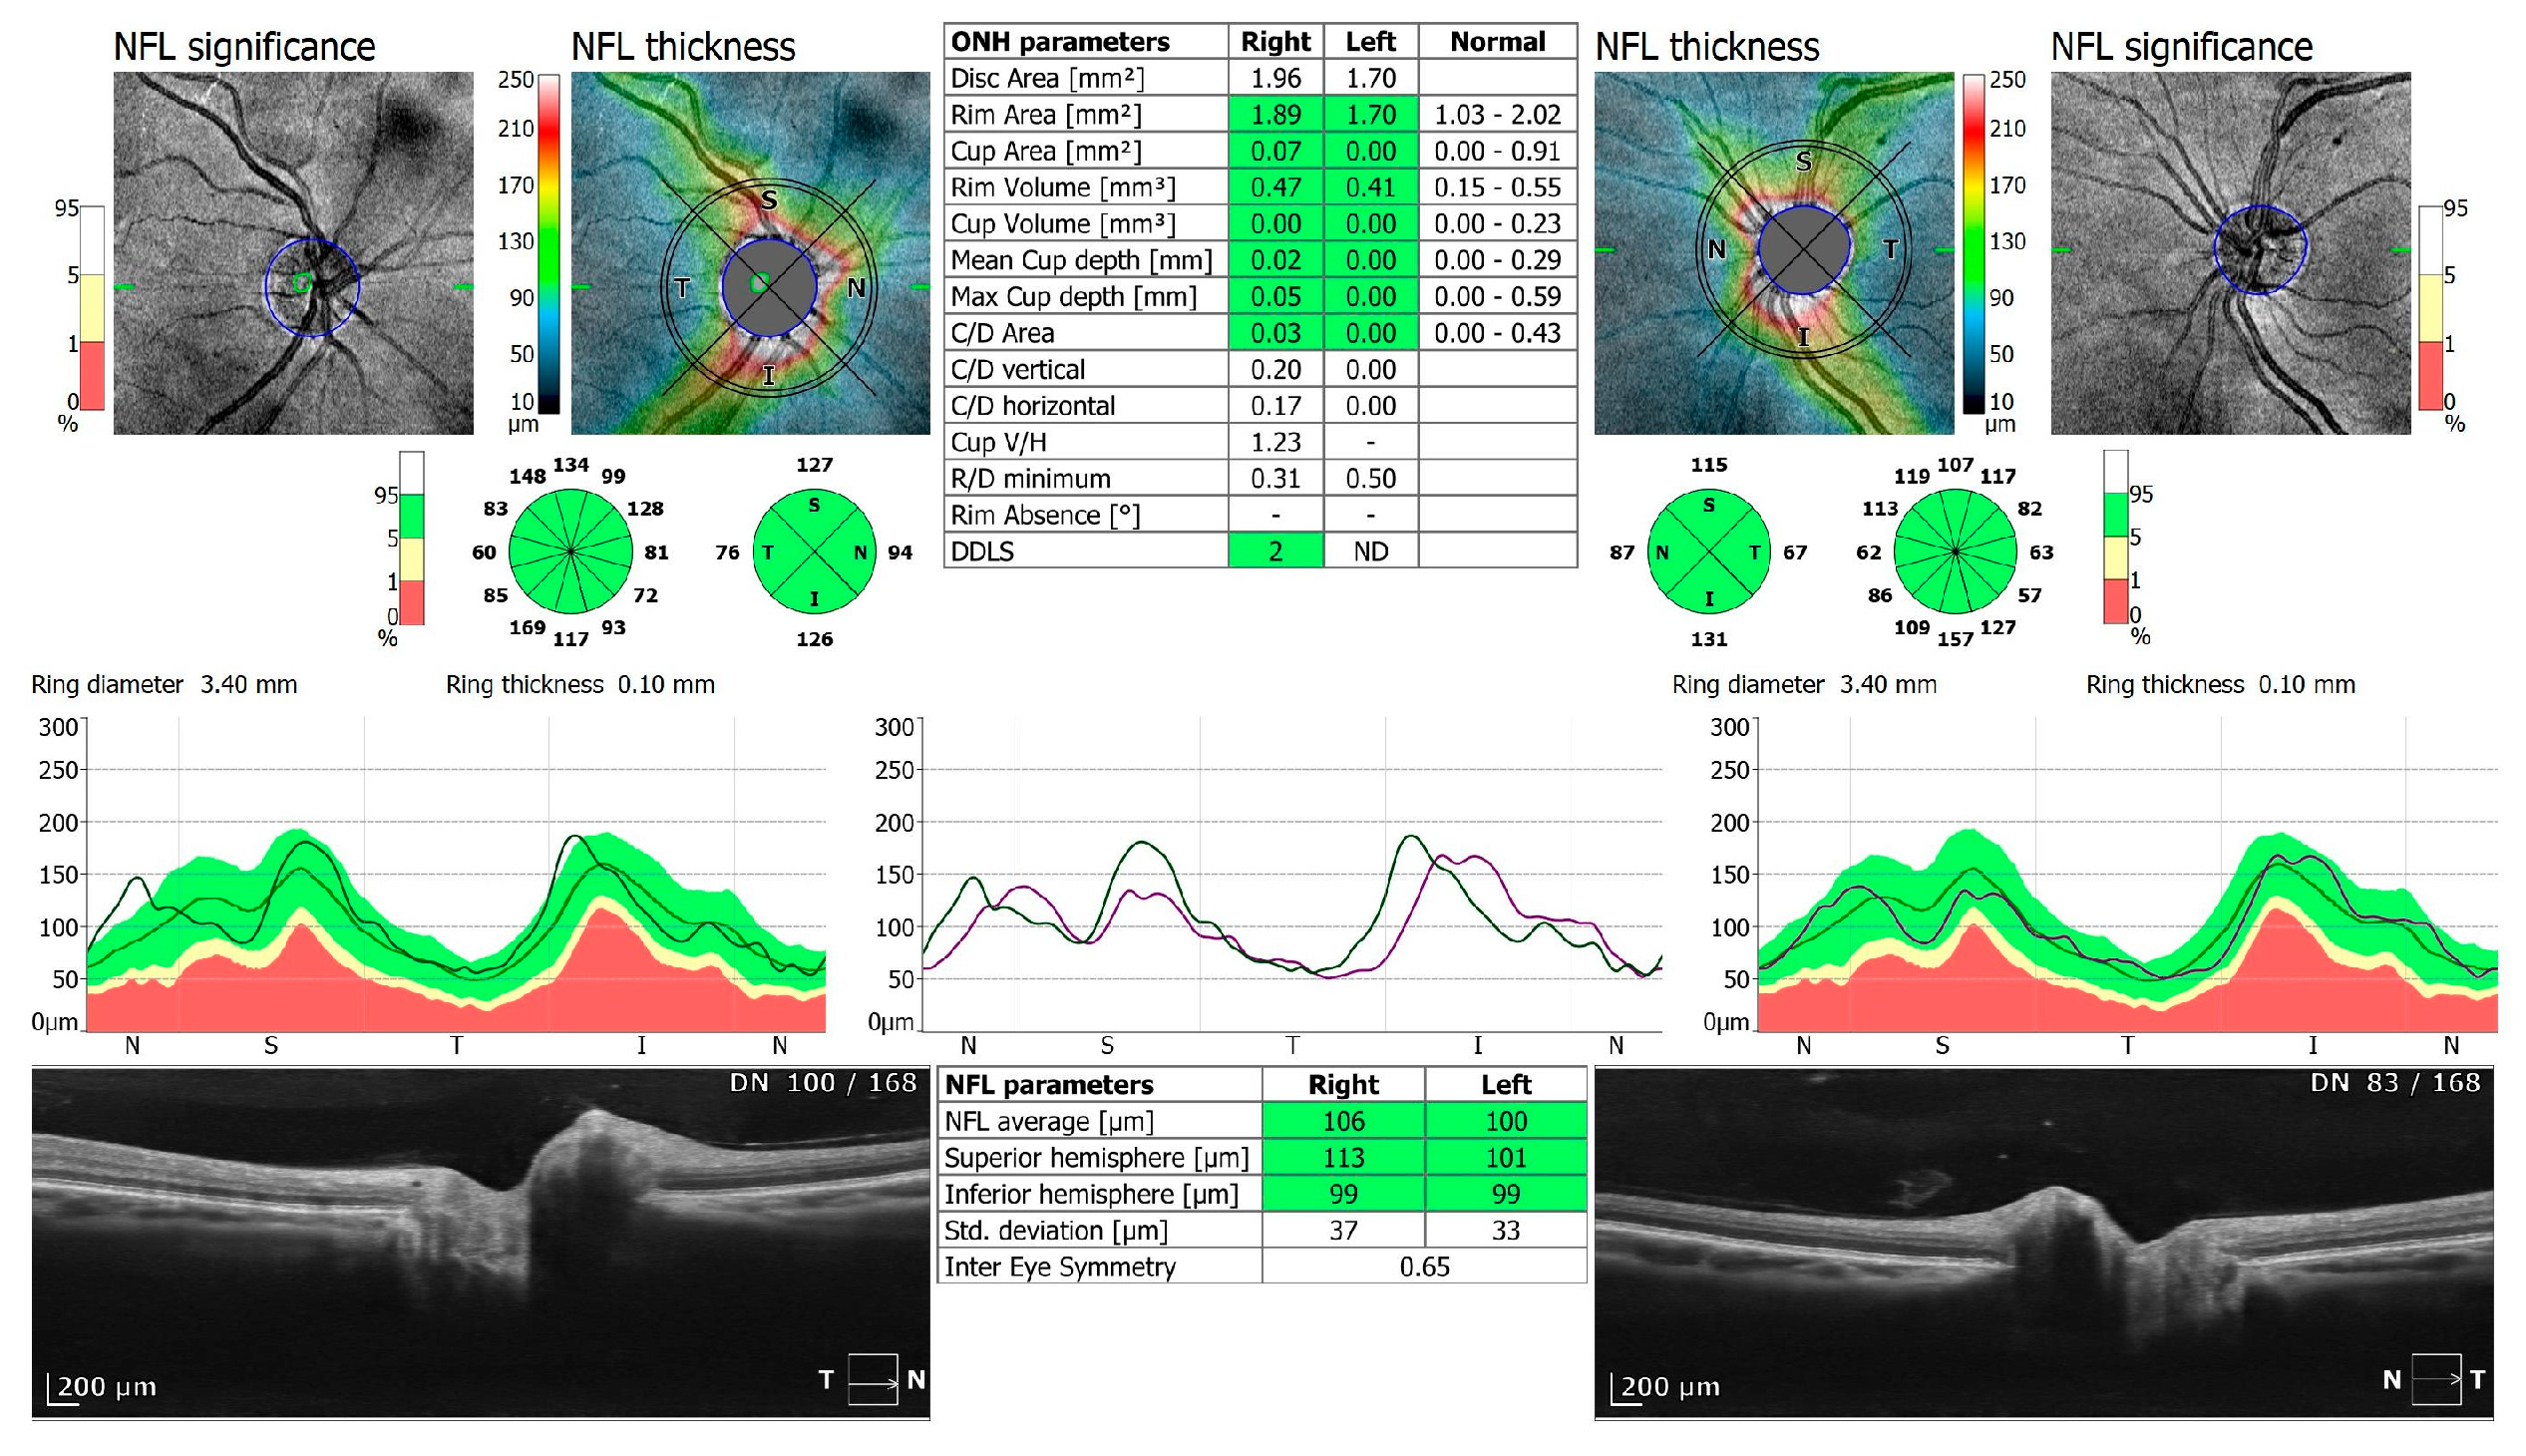

Figure 4.

OCT 3D disc scan 6 × 6 mm of COVID-19 negative patient. NFL, nerve fiber layer; ONH, optic nerve head.